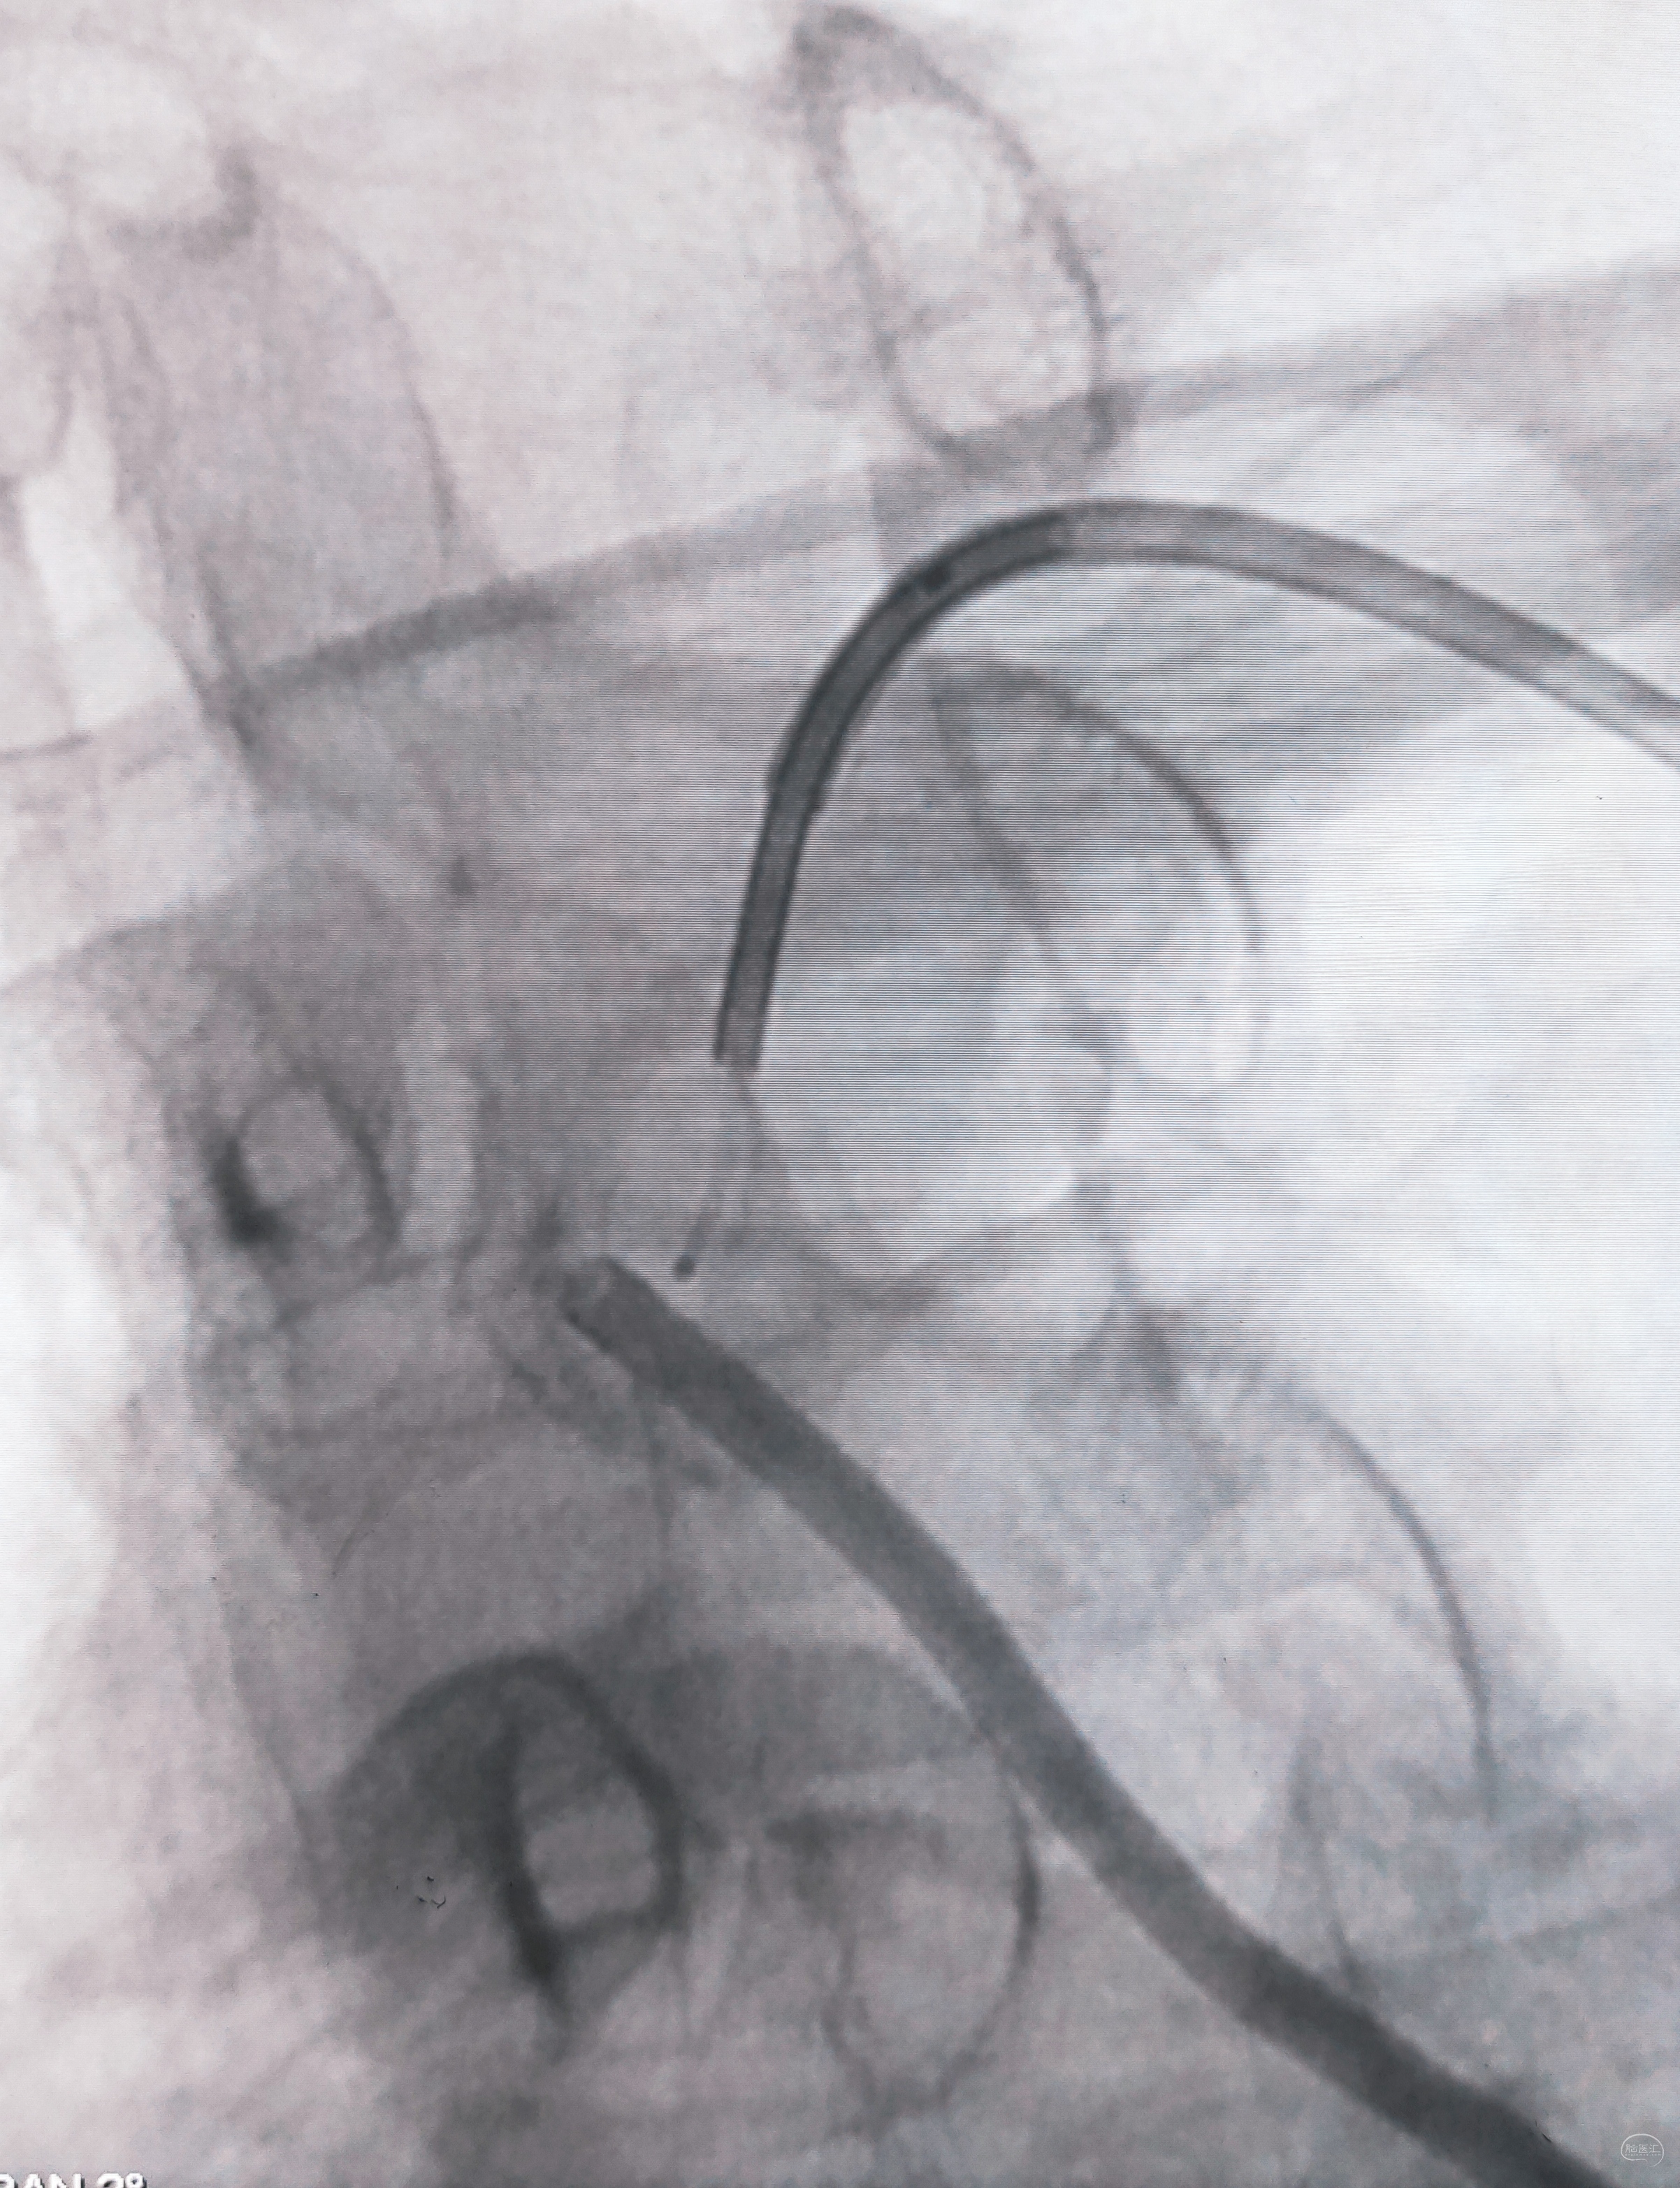

泥鳅两段露头,8F导引导管沿泥鳅攀爬,一把干到左侧肱动脉为止

6F导引导管造影确认支架置入部位

支架导引导管内先通过,再回撤技术,顺利释放雅培9×29球扩支架